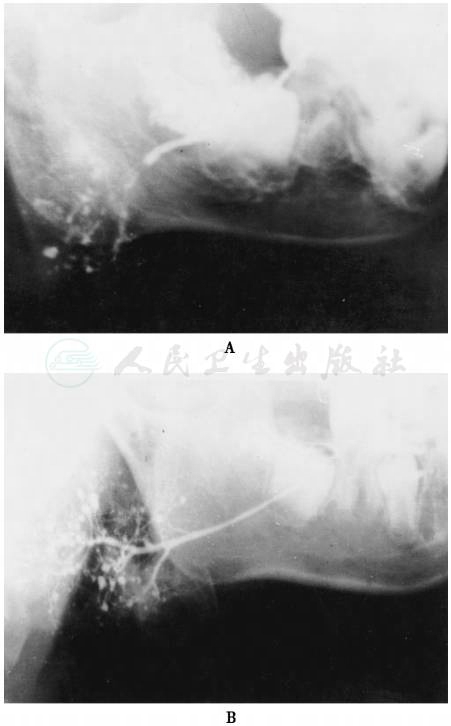

图1 家族性末梢导管点状扩张(腮腺造影侧位)

A.患儿 B.患儿之姐